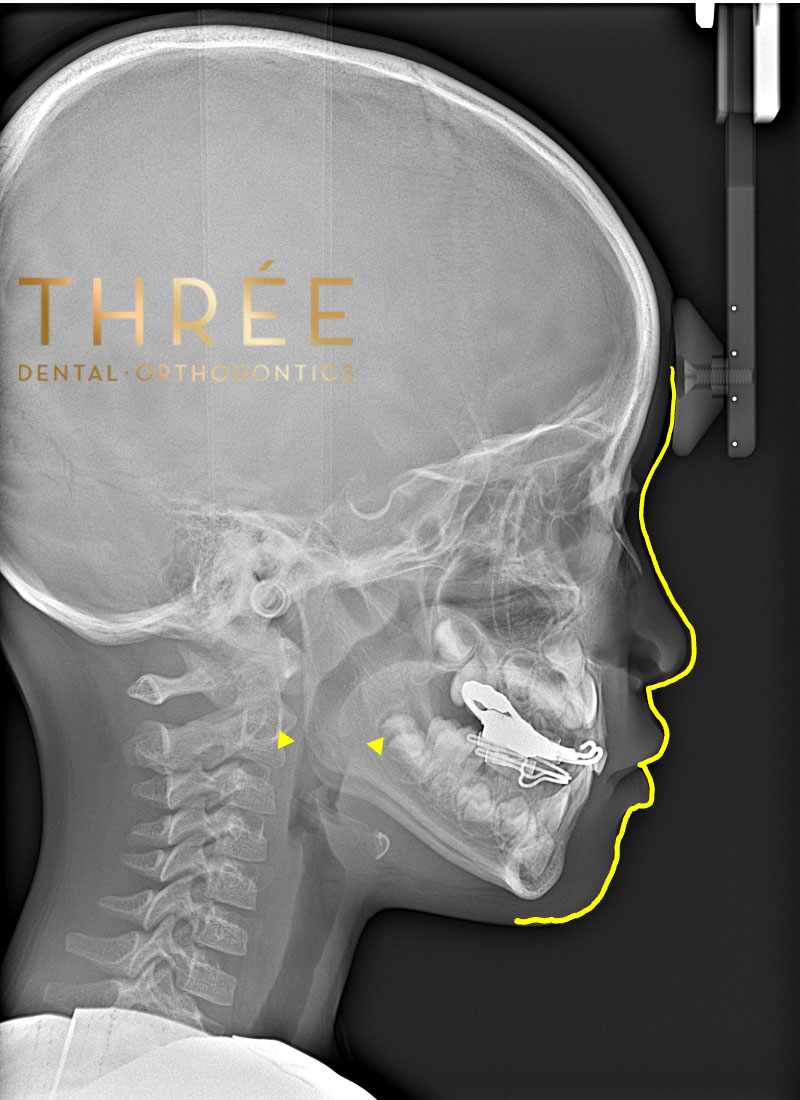

歯並びは顔のパーツに大きな影響を及ぼします。そのため、矯正治療によって口元や顎、横顔が改善されるケースは多いです。特に「口ゴボ」「受け口」「出っ歯」「重度の叢生」は改善することで顔貌の大きな変化が期待できます。

横顔のラインが美しく整い、気道の広がりによる健康的な変化も期待できます。

セファロは、頭蓋骨、顎骨、歯列などの構造を正確に測定し、分析できるレントゲンのことです。セファロ分析により、個々の患者さんの顔面の成長パターン、歯並び、咬み合わせの問題を細かく診断できます。